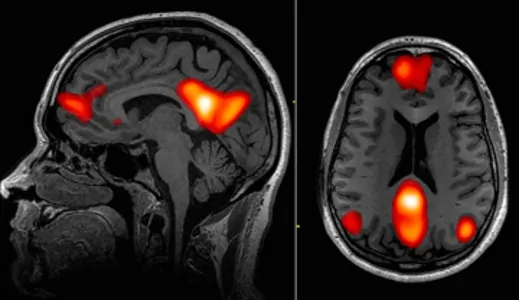

هیپنوتیزم باعث تغییراتی در فعالیت و اتصال مغز میشود که با کاهش خودآگاهی، افزایش کنترل احساسات درونی و نگرانی کمتر سازگار است. مطالعهای که توسط محققان دانشگاه استنفورد در ژوئیه 2016 انجام شد، آنچه را که در طول هیپنوتیزم در مغز اتفاق میافتد، بررسی کرد. تصویربرداری رزونانس مغناطیسی کاربردی (fMRI) برای مشاهده فعالیت مغز در 57 نفر در هیپنوتیزم استفاده شد. تغییرات در سه ناحیه خاص مغز مشاهده شد و نشان داد که:

- کاهش اتصال بین قشر پیشپیشانی - پشتی جانبی (بخشی از شبکه کنترل اجرایی درگیر در برنامه ریزی و تصمیم گیری) و قشر کمربندی خلفی (بخشی از شبکه حالت پیش فرض فعال در طول تفکر مرتبط با خود). این ارتباط کاهشیافته بین برنامهریزی اقدامات و خودآگاهی ممکن است دلیل فوری بودن عملی باشد که در طول هیپنوتیزم انجام میشود. در هیپنوتیزم، مانند حالتهای جذب عمیق در یک کار یا عملکرد، شخص به طور خود به خودی عمل میکند، بدون اینکه در مورد اعمال فکر کند.

- افزایش اتصال بین قشر جلویی پیشانی - پشتی جانبی (بخشی از شبکه کنترل اجرایی درگیر در برنامه ریزی و تصمیمگیری) و اینسولا (بخشی از شبکه برجسته که در حس کردن و تنظیم فرآیندهای درونی بدن نقش دارد) این ممکن است مسئول افزایش کنترل بر فرآیندهای بدنی و عاطفی در هیپنوتیزم باشد.

- کاهش فعالیت در قشر کمربندی قدامی پشتی (بخشی از شبکه برجسته که در ارزیابی احساسی خطاها و نگرانیها نقش دارد). ACC پشتی نیز در حین عملکرد پر تلاش فعال است. این کاهش فعالیت ممکن است توضیح دهد که چرا در هیپنوتیزم و حالتهای جذب عمیق، اعمال و عملکرد بدون زحمت و با نگرانی کمتر انجام میشود.

کاهش فعالیت در بخشهایی از شبکه حالت پیشفرض مغز (DMN) باعث افزایش جذب توجه میشود.

DMN شبکهای از نواحی مغزی متقابل است و زمانی فعال است که فرد درگیر کاری نیست و در هنگام فکر کردن، به خاطر سپردن و رویاپردازی است. DMN زمانی که فردی درگیر یک کار هدفمند باشد یا توجه او کاملاً جذب چیزی شده باشد فعال نیست. هیپنوتیزم فعالیت DMN را کاهش میدهد. کاهش فعال شدن DMN در تمرین کنندگان طولانی مدت مدیتیشن نیز مشاهده میشود. این واقعیت که مغز تحت هیبنوتیزم کاهش فعالیت DMN را نشان میدهد، از تعریف هیپنوتیزم به عنوان یک حالت جذب توجه پشتیبانی میکند، نه حالتی که در آن فرد هوشیاری خود را از دست میدهد. هیپنوتیزم پاسخهای عصبی مشابه تفکر مفهومی خود به خودی را نشان میدهد. شاید به همین دلیل است که هیپنوتیزم میتواند خلاقیت و بینش را برانگیزد.

افزایش فعالیت در سیستمهای توجه ناحیه جلویی (فرونتال) مغز باعث افزایش عملکرد اجرایی میشود.

نواحی جلویی مغز در توانایی فرد برای تمرکز، که به عنوان کنترل توجه شناخته میشود، نقش دارند. کنترل توجه ارتباط تنگاتنگی با کارکردهای اجرایی مانند استدلال، حل مسئله، برنامهریزی، خودکنترلی و انعطاف پذیری شناختی (توانایی تفکر همزمان درباره چندین مفهوم) دارد. هیپنوتیزم فعالیت سیستمهای درگیر در این عملکردها را افزایش میدهد و در اعتیاد و ADHD دچار اختلال میشوند.

هیپنوتیزم فعالیت را در نواحی مغز که در تنظیم هوشیاری دخیل هستند تعدیل میکند.

اسکن PET از جریان خونی - مغزی در هیپنوتیزم، درگیری قشر کمربندی قدامی (ACC)، تالاموس و ساقه مغز پانتو - مزانسفالیک را نشان میدهد. هیپنوتیزم جریان خون را در ناحیه اکسیپیتال افزایش میدهد و این مسئله با این تئوری که هیپنوتیزم برانگیختگی قشر مغز را کاهش میدهد (یعنی نظریه مهار قشر مغز) مطابقت دارد. افزایش جذب ذهنی در طول هیبنوتیزم با افزایش جریان خون در سیستم توجه مغز مرتبط است.